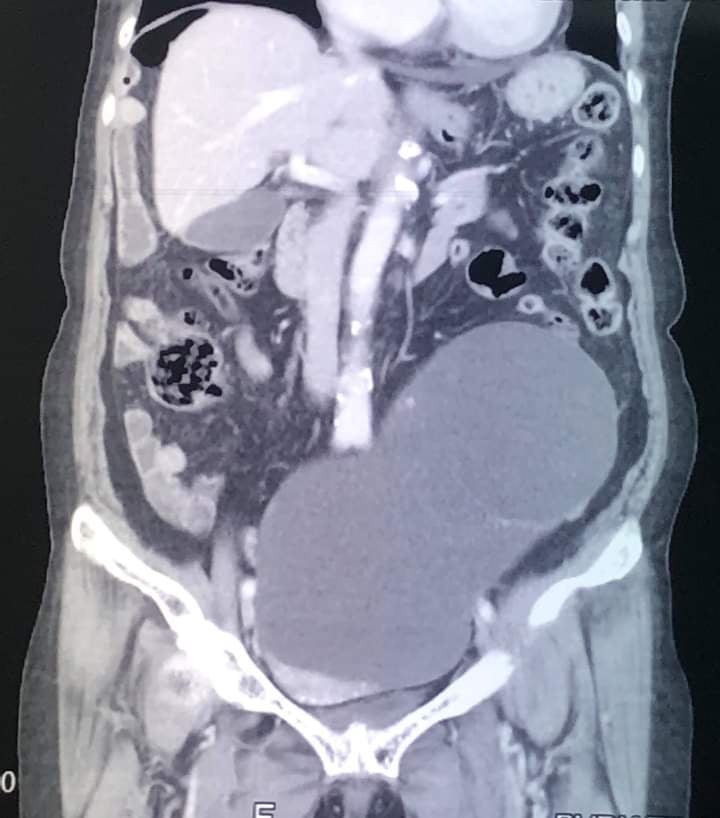

Tiếp nhận bệnh nhân, các bác sĩ tiến hành thăm khám lâm sàng phát hiện bụng bệnh nhân to, có khối u vùng bụng dưới qua khỏi rốn, ấn khá đau. Chụp cắt lớp vi tính xác định, khối u dạng dịch vùng tiểu khung lệch khá to.

Ngay sau đó, bệnh nhân được chỉ định phẫu thuật nội soi. Quá trình thực hiện, quan sát thấy khối u sau phúc mạc nằm vùng tiểu khung chiếm gần hết ổ bụng dưới rốn (ước lượng khoảng 3kg).